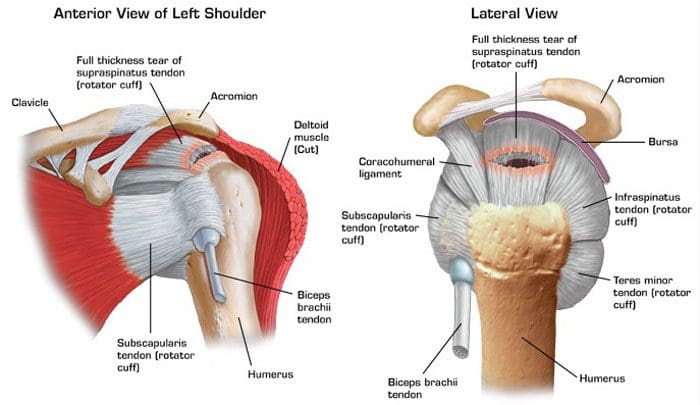

Фотографии мышц ротаторной манжеты плеча